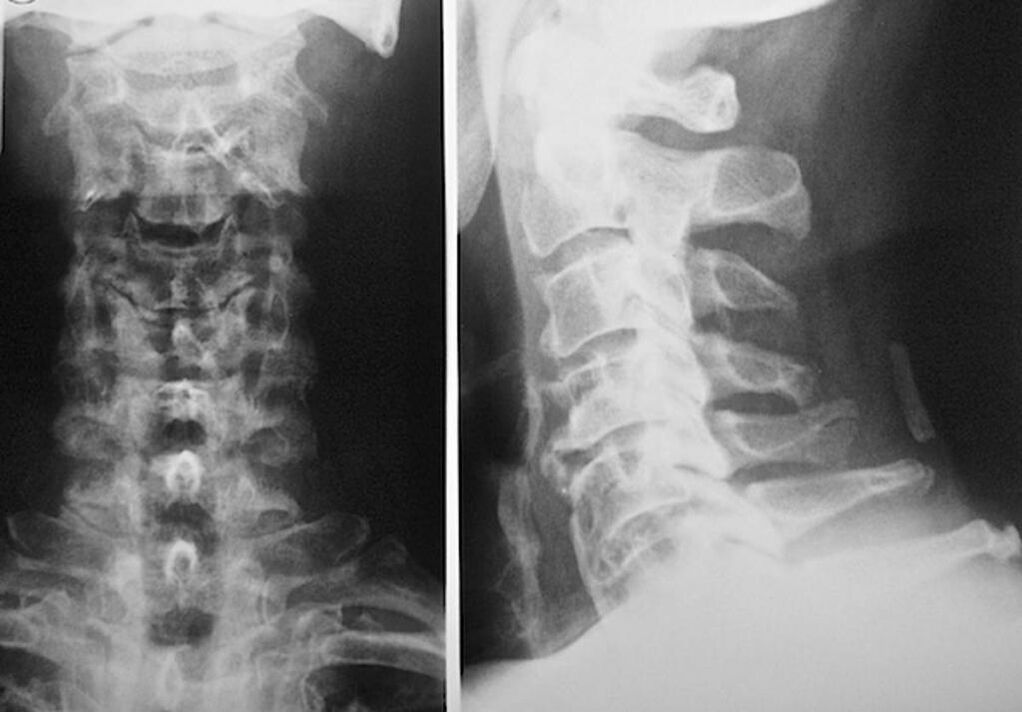

Siekiant diagnozuoti ir tiksliai įvertinti tarpslankstelinių diskų būklę, naudojami šie tyrimo metodai:

- Radiografija.

- KT skenavimas.

- Magnetinė tomografija.

- Ultragarsinis kaklo kraujagyslių skenavimas.

Kiekvienas iš jų yra visiškai saugus sveikatai ir nekelia per didelio poveikio grėsmės. Kaklo slankstelių osteochondrozės diagnozė, kurios gydymas bus vykdomas visą likusį gyvenimą, gali būti atlikta po paprasto vizualinio patikrinimo. Bet kuris ortopedas gali lengvai tai padaryti. Išimtis – pirmoji ligos stadija, kai nepastebima jokių matomų gimdos kaklelio srities patologijų.